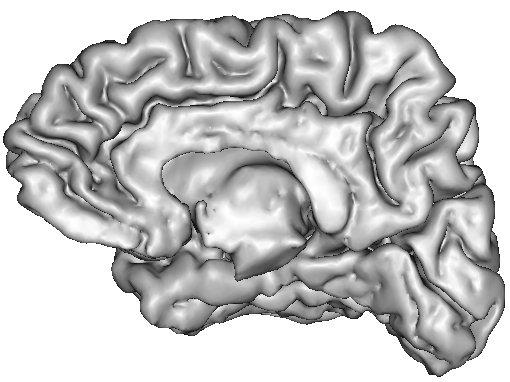

The resulting grey/white interface can be converted into a mesh endowed with the spherical topology, which will be inflated by some other Brainvisa treatments for visualization purpose (Ana Inflate Cortical Surface):

A dilation of this interface towards the outer brain edges may lead to nice 3D rendering of the cortical surface, which are easy to read because the folds are opened (Ana Get Opened Hemi Surface) :